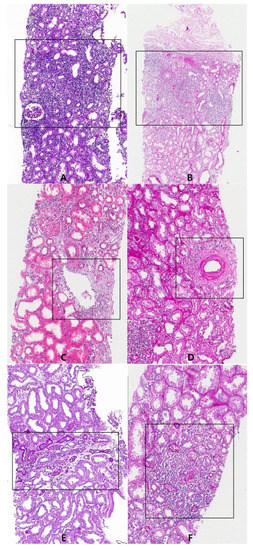

2.2. Patient Selection Criteria and Tissue Pathology Grading

2.5. Region of Interest (ROI)